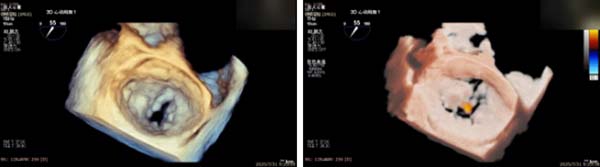

手术过程中,麻醉与围术期医学科副主任医师马金本确保麻醉过程平稳。心脏大血管外科主治医师董明亮穿刺股静脉置入血管鞘,并在心脏超声科梁皓主任及段福建教授TEE引导下,顺利穿刺房间隔,房间隔穿刺高度4.9cm。随后,在王安彪主任以及刘洋教授指导、心脏超声科梁皓主任TEE引导下,董明亮医师沿输送系统将延展呈“一字型”状态的国产夹合器送至左房,缓慢关闭夹合器并进行弹道测试。调整夹合器位置和方向后,董明亮医师再次将夹合器延展呈“一字型”完成跨瓣,避免发生腱索缠绕,成功捕获瓣叶后关闭夹合器,二尖瓣反流显著下降。夹合器完全解离后,超声示二尖瓣反流程度显著下降,残余反流0,平均跨瓣压差1mmHg,手术圆满成功。

解离前三维

解离后瓣叶及反流

解离后三维